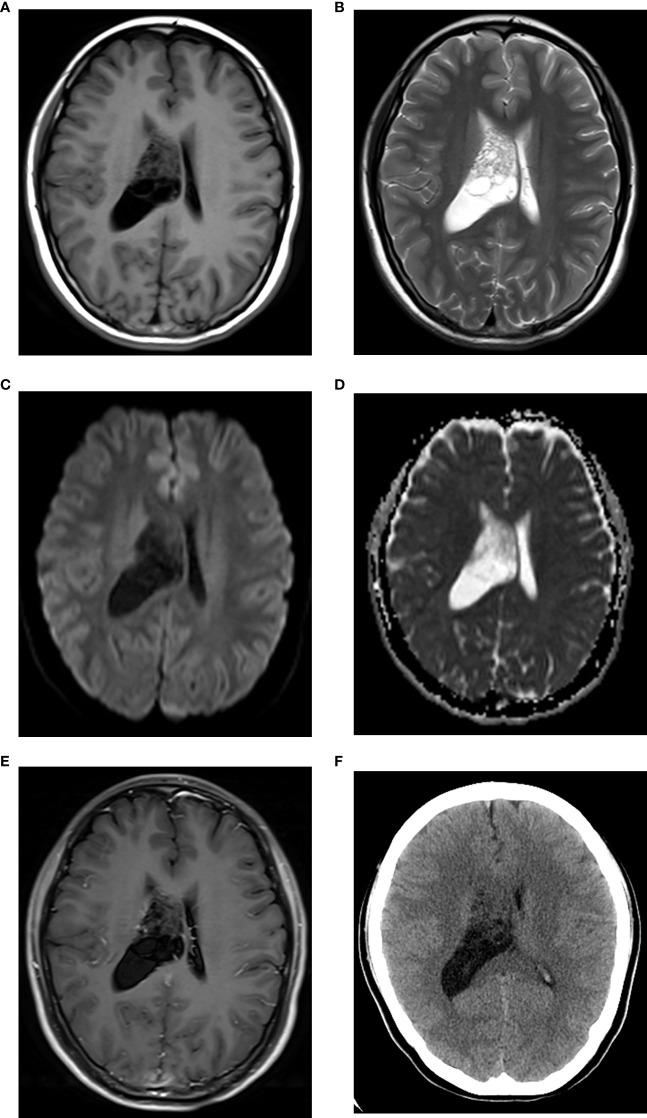

Imaging characteristics of central neurocytomas according to Ki-67 proliferation index.

Compared to CNs with low Ki-67, CNs with high Ki-67 were larger (P < 0.001) and more solid (P = 0.019). Restricted diffusion (P = 0.020), CT hyperdensity (P < 0.001), abnormal vessels (P = 0.018), and marked MRI enhancement (P < 0.001) were more common in CNs with high Ki-67.

Different Ki-67 indices could affect the imaging characteristics of CNs. Tumor size, radiologic solidity, abnormal vessels, and marked MRI enhancement suggested CNs with high Ki-67. Combining these imaging characteristics and Ki-67 indices offered meaningful insights into their clinical diagnosis and biological behavior.